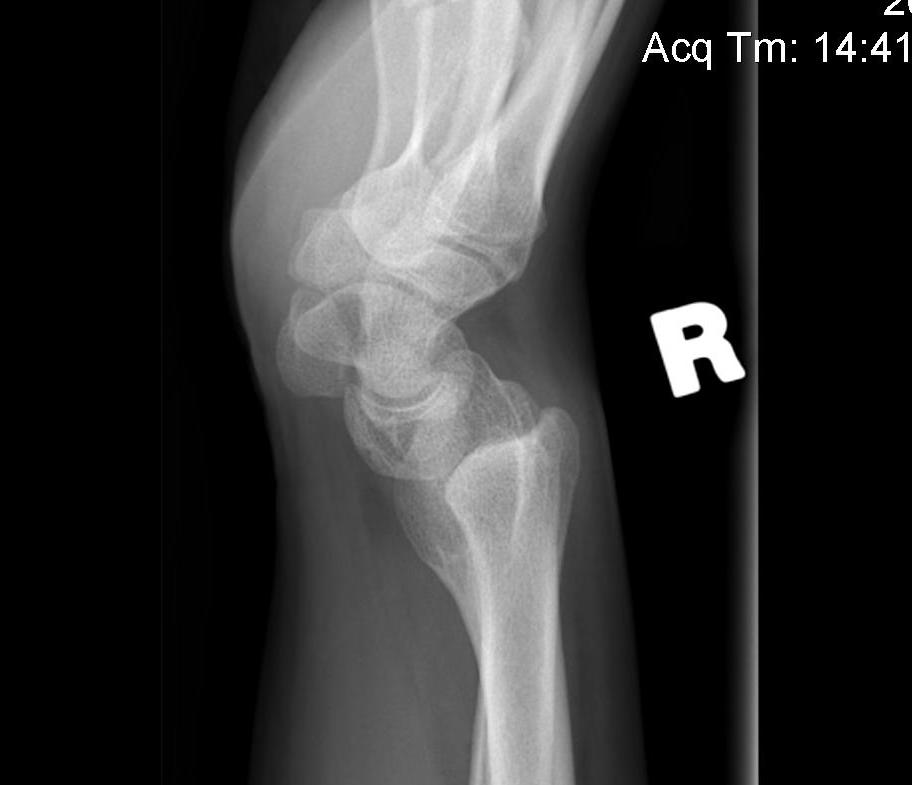

X-ray

Volar-ulna tilt of the distal radius with dorsal subluxation of ulna / distal radius triangular shape

Proximal carpal row becomes wedge shaped

- lunate "falls into" the radio-ulna gap

DRUJ widened

Chevron

- proximal carpal row distorted / V-shape

- lunate in apex between radius and ulna